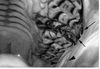

Figure 29-33. The occlusal surface of this cheek tooth (06s have six pulp horns) has intact secondary dentine over five pulp cavities, but has a pulp exposure over one (pulp horn five, with needle inserted) indicative of chronic pulpar death. Some localized caries is present in both infundibulae.